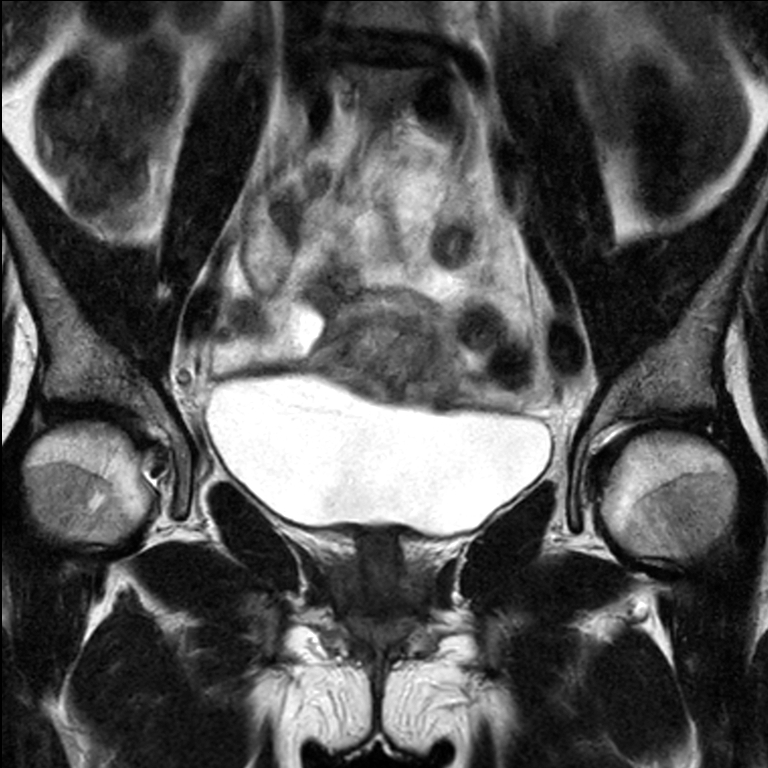

Patient diagnosed with cervical cancer referred for external beam radiotherapy. Three MRIs with different bladder filling were acquired: Half full (mid), empty and full bladder. Patient was imaged at Ingenia MR-RT 1.5T using FlexCoverage Anterior Coil in combination with the integrated Posterior Coil.

Coronal T2w TSE mid